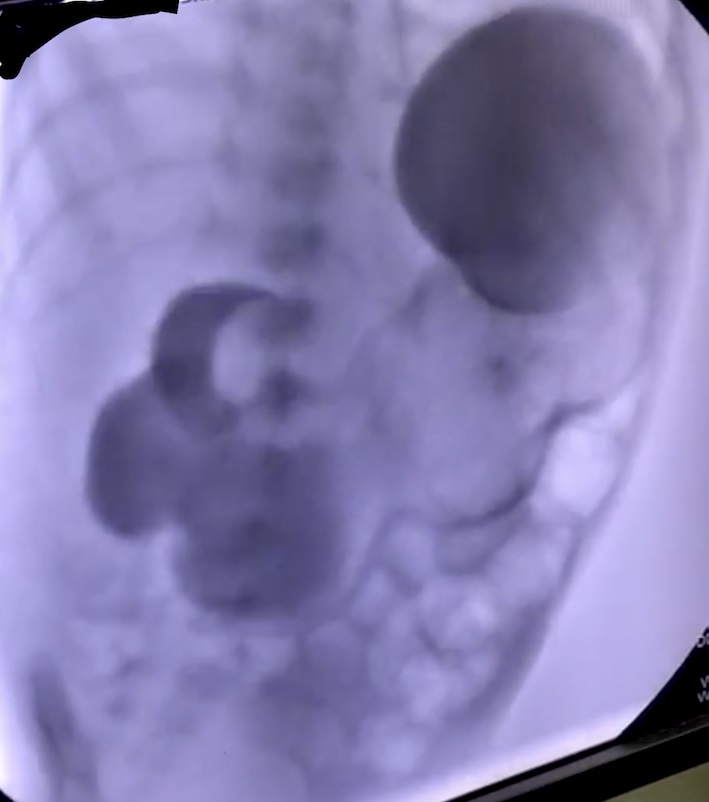

On arrival, the child weighed 2.6kg, heart rate was 124 per minute, respiratory rate was 40 per minute and there was mild dehydration. Oxygen saturation was 98% on ambient air. The abdomen was not distended, there was no visible peristalsis, no mass palpable per abdomen, and bowel sounds were normal. On the X-ray abdomen, the stomach appeared distended and there were a few air shadows in the small bowel. On Ultrasonography (USG) of the abdomen, there was a cystic lesion with bowel signature measuring 12.1mm x 20.6mm x 22.5mm, inferomedial to gall bladder suggestive of enteric duplication cyst. Venous blood gas analysis revealed mild alkalosis with a pH of 7.46. Serum sodium was 133mEq/L and serum potassium was 3.5mEq/L. On oral contrast study, there was no flow of contrast distal to the second part of the duodenum (Fig. 1).

Figure 1

Oral contrast study on fluoroscopy: No flow of contrast distal to the second part of the duodenum.